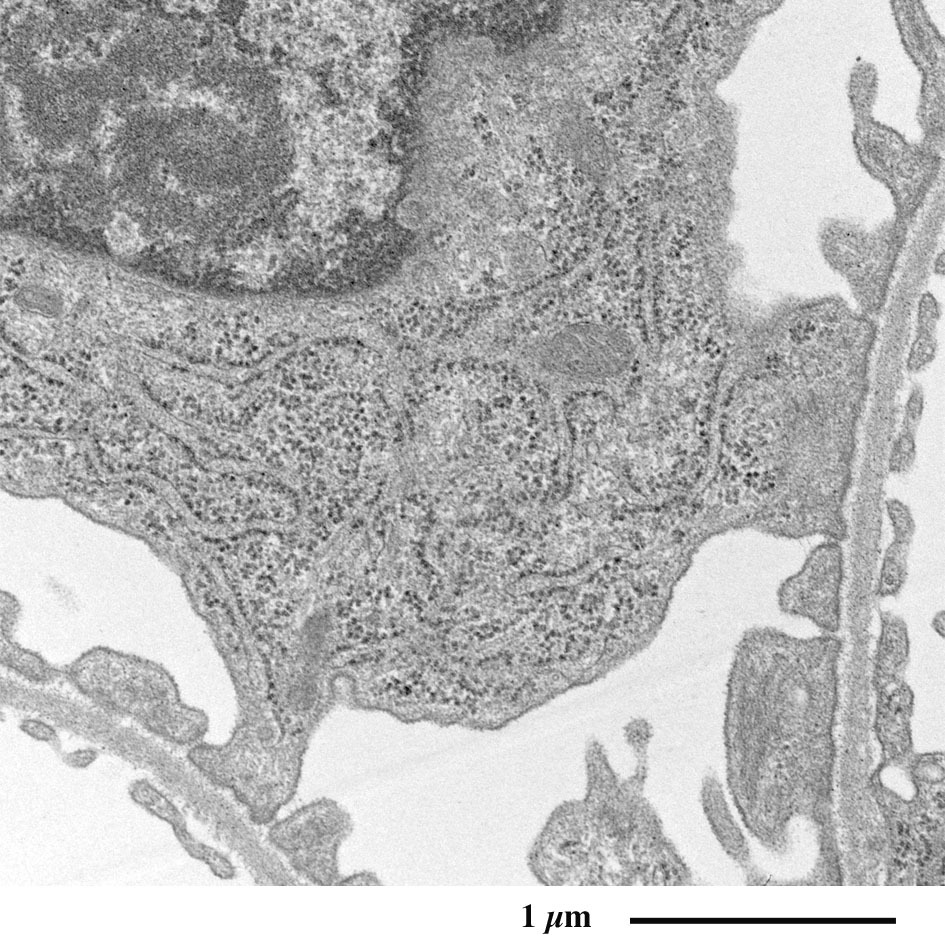

相互嵌合的足突

(放大图像)

肾小球的有孔毛细血管

(外周被足突包绕的毛细血管壁截面)